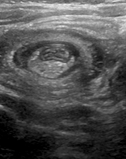

Κλασική υπερηχογραφική εικόνα εντύλιξης λεπτού εντέρου (Ευγενική παραχώρηση Dr. V. Penopoulos)